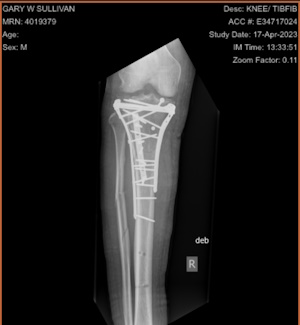

This story is not tech related but vital for me to write about anyway. On February 25th, while skiing at my home mountain, Wildcat, in New Hampshire, I fell awkwardly and shattered my tibia and broken fibula. After a six-hour surgery to repair everything, I had an extended hospital stay and a painful and exhausting rehab stint. During this journey, I discovered an often-overlooked truth: we take our everyday blessings for granted. It was easy to overlook the privilege of effortless mobility when my own was unaffected, but now, a shattered leg and a frame of steel serve as reminders of what was once effortless.